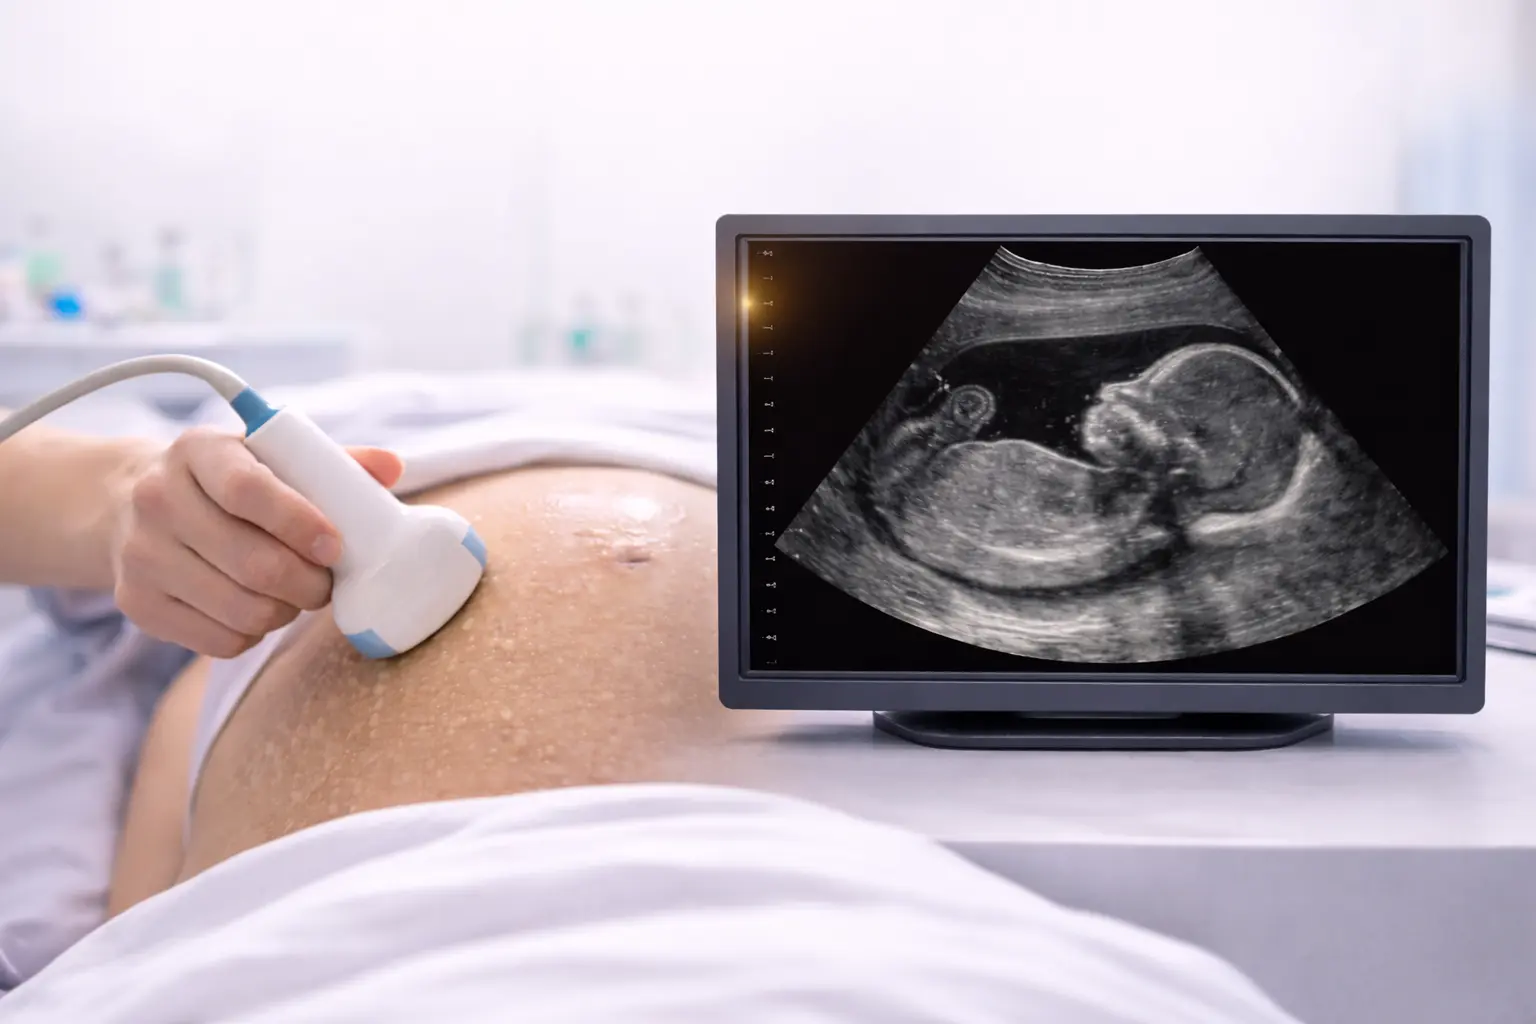

What Can an Early Pregnancy Scan Tell You?

An early pregnancy scan can provide valuable information during the first weeks of pregnancy, offering both reassurance and medical insight at an important stage. Typically